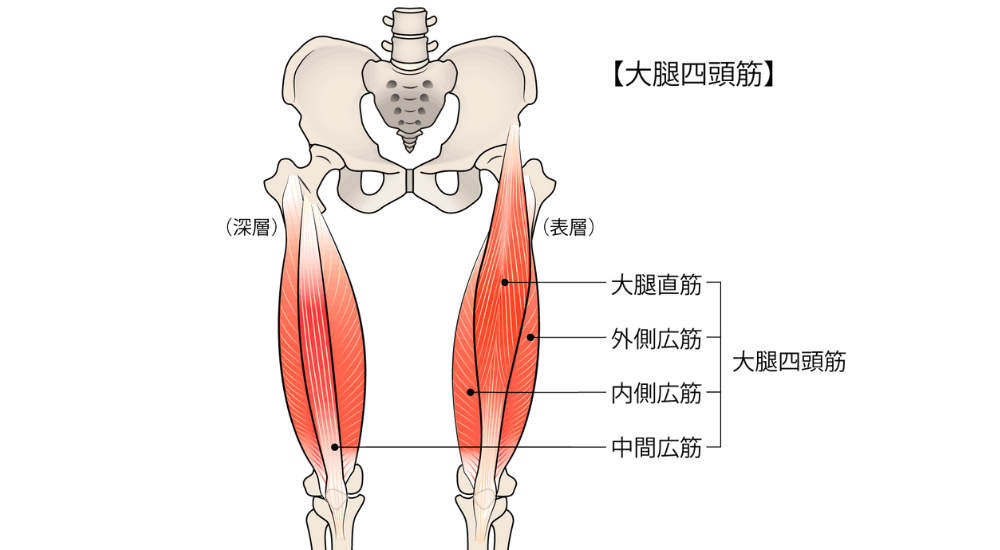

- 大腿四頭筋(特に大腿直筋): 太ももの前。股関節にもまたがるため、反り腰に伴う骨盤前傾の影響で硬くなりやすいです。